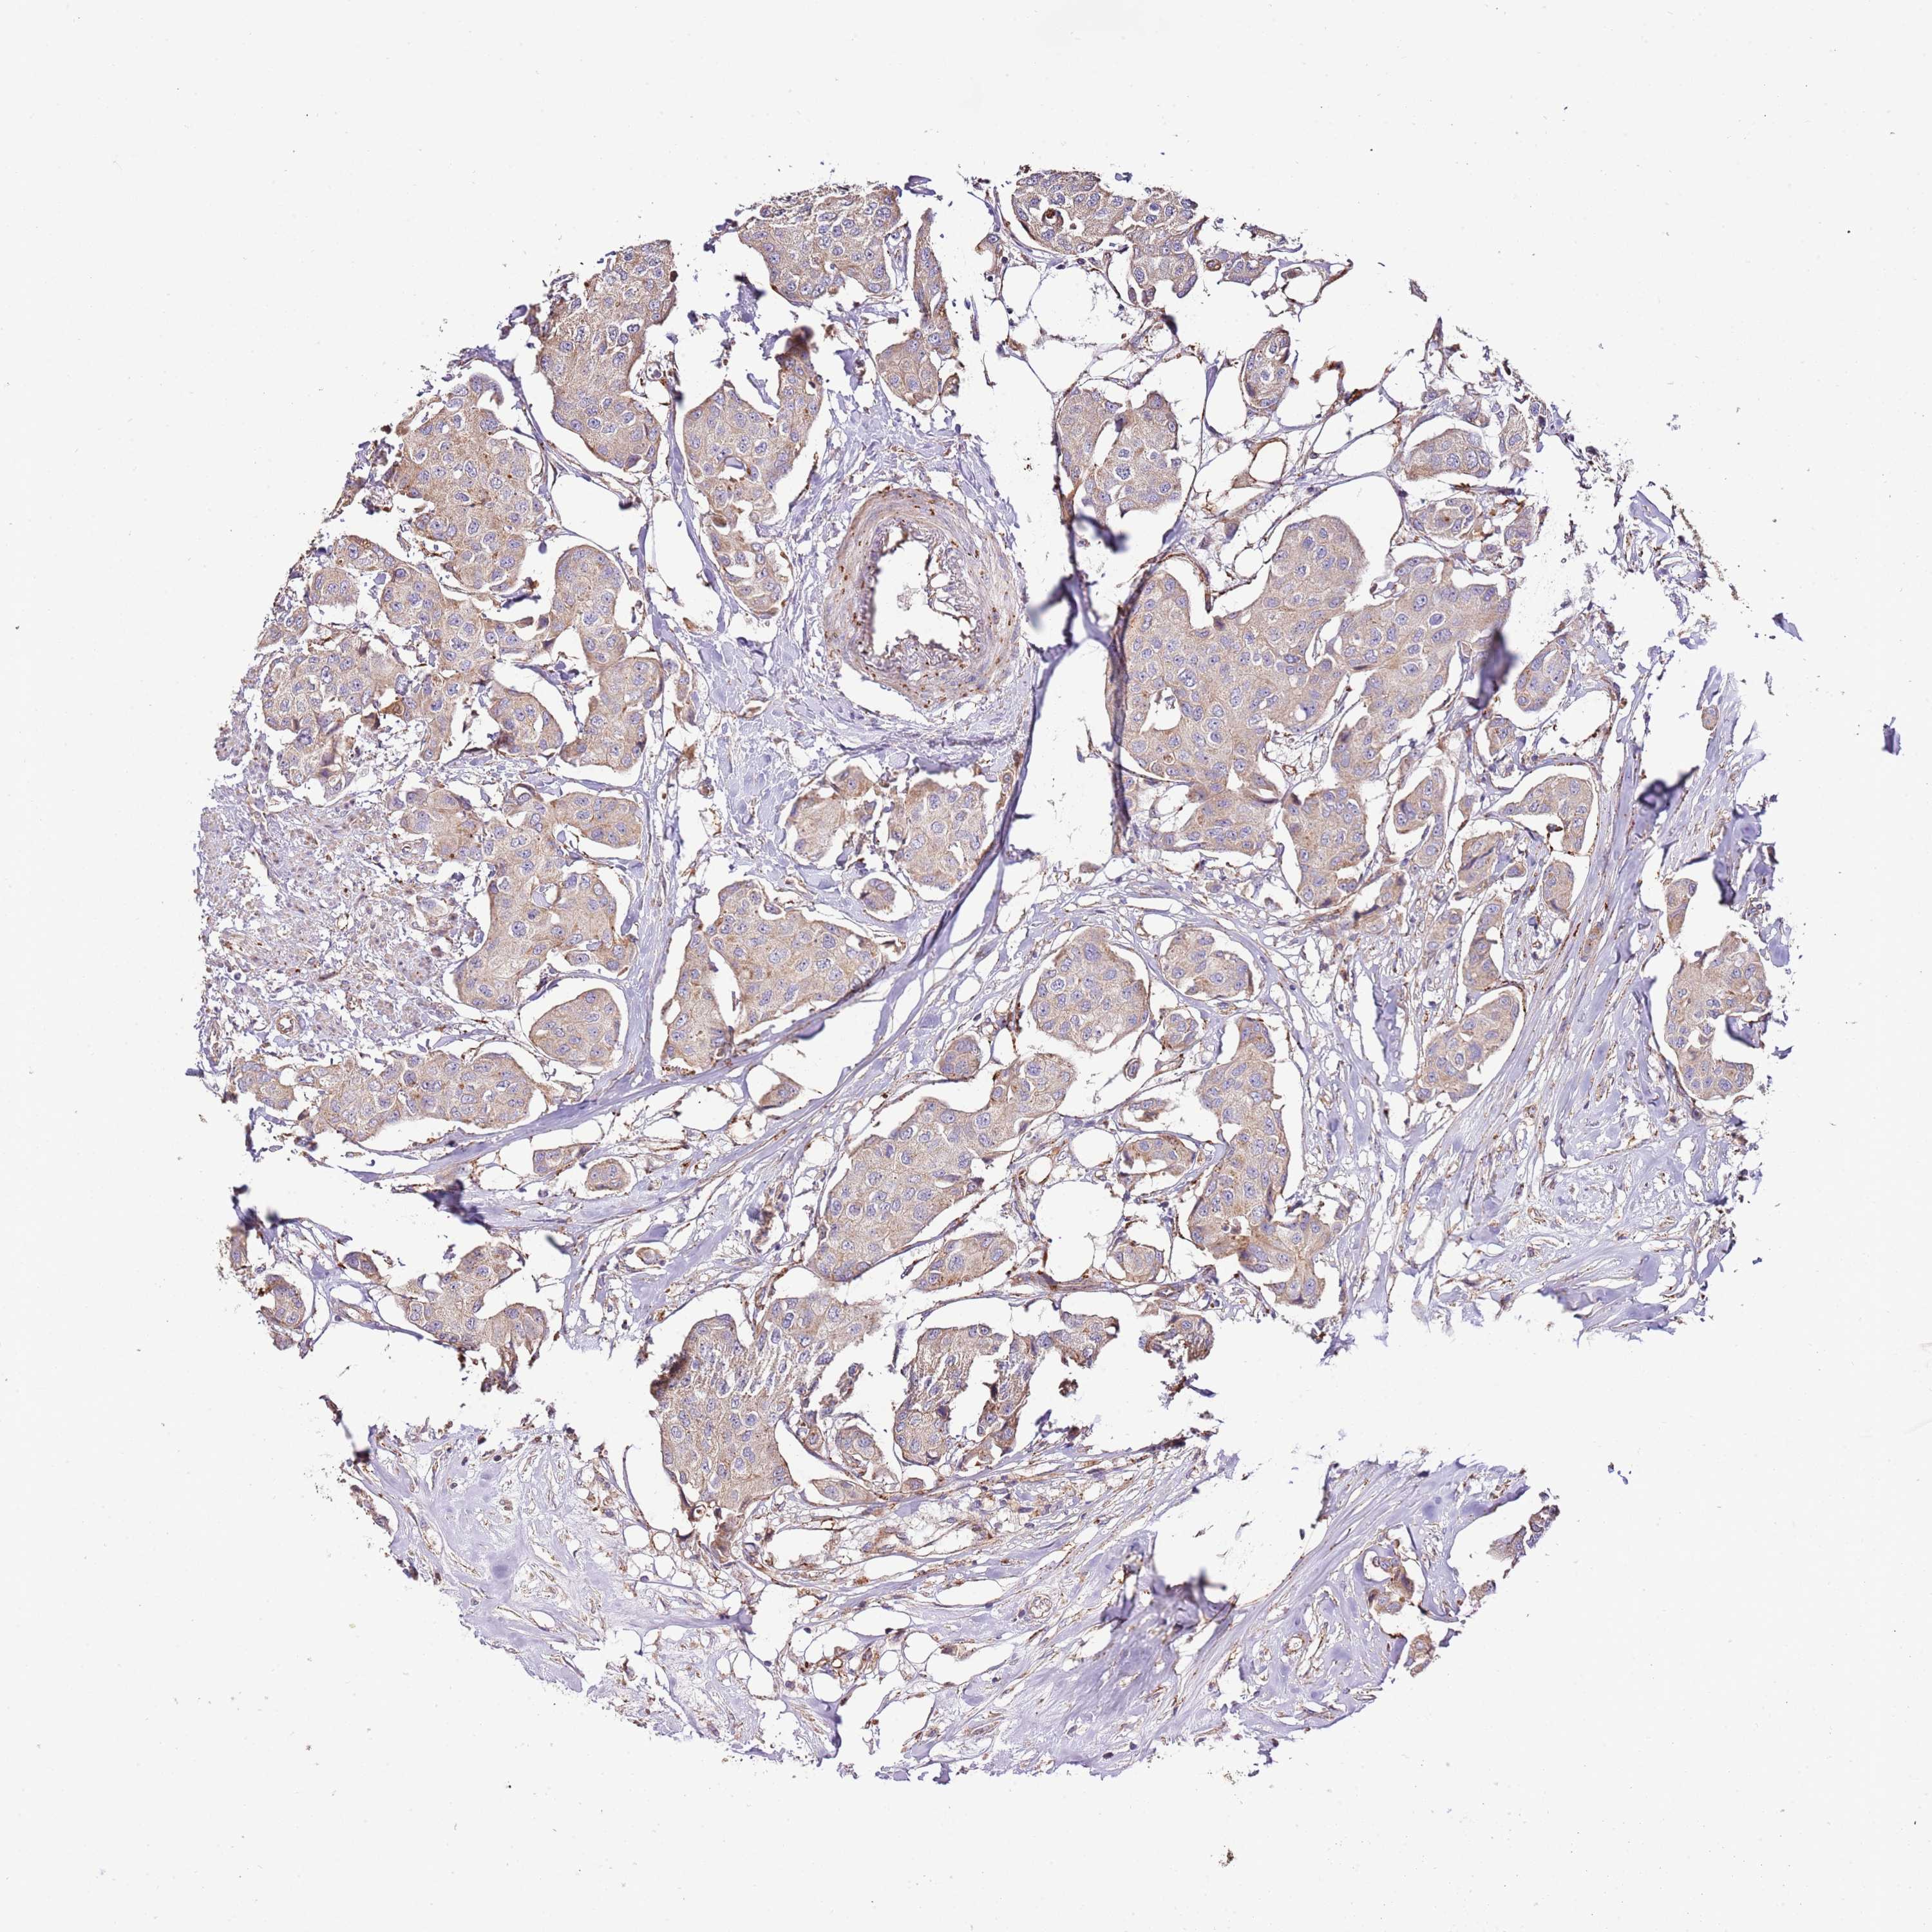

CANCER BREAST CANCER Show tissue menu

BRCA TCGA BRCA VALIDATION PROTEIN EXPRESSION

Breast cancer

Human cancer

Breast invasive carcinoma